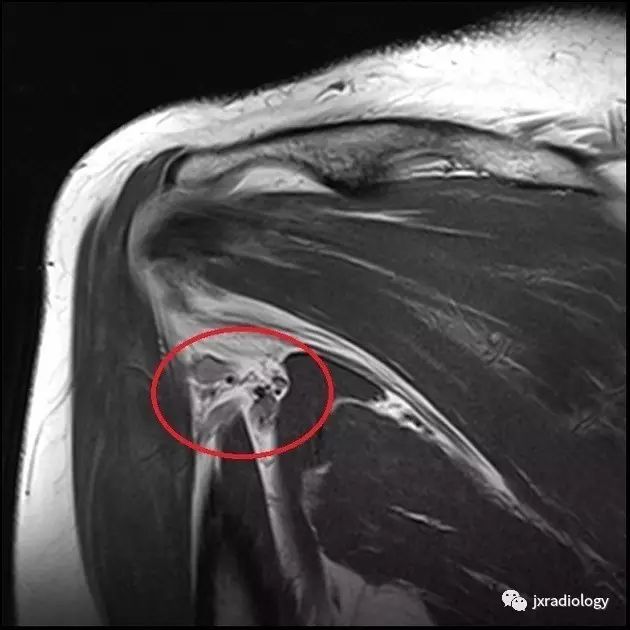

MRI is the investigation of choice, demonstrating atrophy +/- fatty infiltration in the teres minor and/or deltoid muscle. Literature review has shown varying proportions of deltoid and teres minor involvement.

MRI是首选的检查,表现为小圆肌和/或三角肌的萎缩+/-脂肪浸润。文献综述显示不同程度的三角肌和小圆肌的不同程度的受累。

MRI Scan showing atrophy of Teres Minor(小圆肌萎缩)